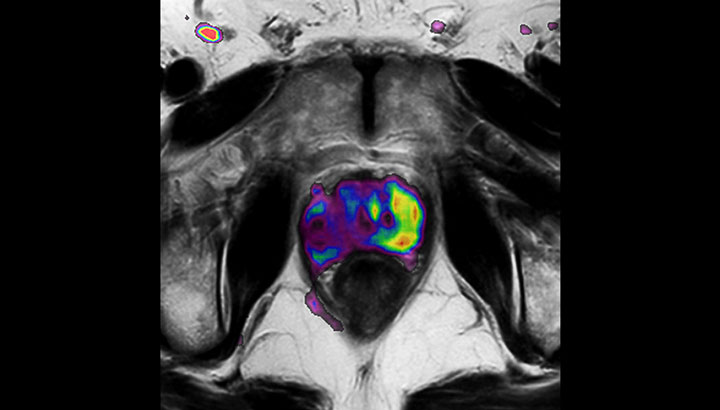

With its exceptional soft-tissue visualization capabilities and wide range of image contrasts, MRI has become a powerful tool to help more precisely define tumor boundaries. This is particularly important as it has been established that there is a high degree of uncertainty in target volume delineation, and it is even reported to represent the largest uncertainty in the entire radiotherapy process for most tumor sites**. Better visualization of the target area and nearby organs-at-risk is a key factor in enhancing target volume delineation. MRI’s expanding role also can be attributed to its functional imaging capabilities, which can inform both target characterization and treatment response.

Our innovative MRCAT (MR for Calculating ATtenuation) clinical applications lets you plan radiation therapy using MRI as primary imaging modality. Within just one, fast MR exam, MRCAT provides both excellent soft-tissue contrast for target and OAR delineation and CT-like density information for dose calculations.